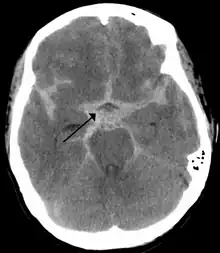

Selected image –

Photo credit: Public domain (U.S. Brookhaven National Laboratory)